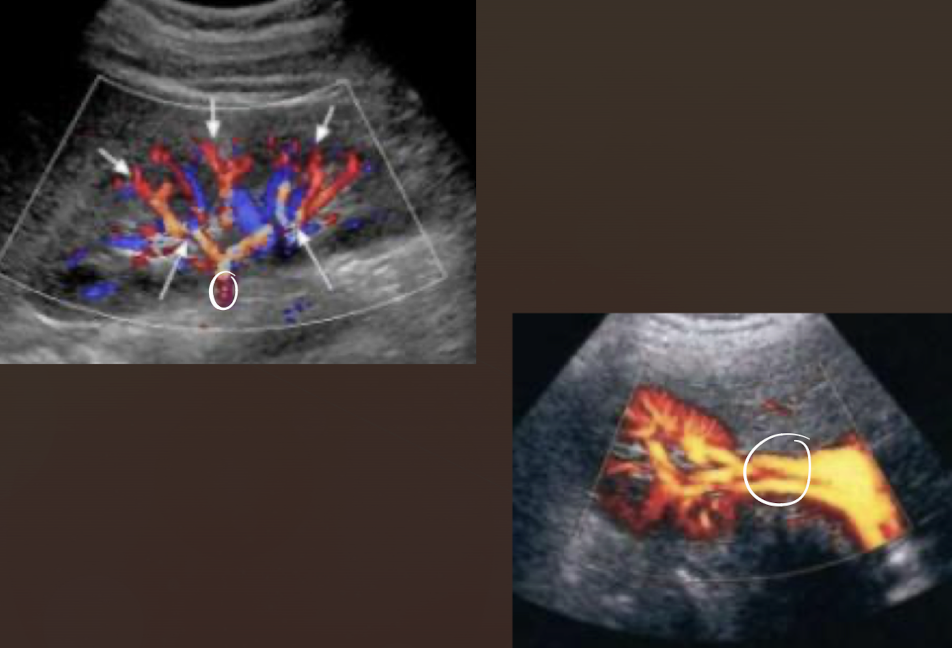

renal vasculature

M.S.I.A.I.

main renal artery

segmental renal artery

at hilum

interlobar arteries

between/along pyramids

arcuate arteries

at base of pyramids

interlobular arteries

near edge of cortex

what is the course of the RRV?

RRV extends from central renal sinus directly into IVC